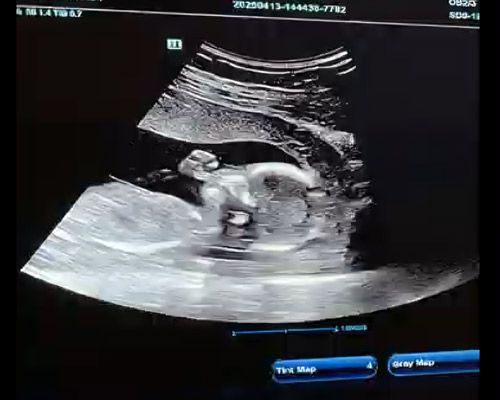

Ultrasound scanning is a widely used imaging method that allows specialists to see what is happening inside the body using high-frequency sound waves. It is one of the most reliable ways to observe development and monitor progress at different stages. During an appointment, a trained sonographer uses a handheld device called a probe or transducer. This device is moved gently across the abdomen, sending sound waves into the body. The returning echoes are then converted into live images displayed on a screen.

The probe is then gently moved across the area, creating real-time images on the monitor. During the scan, you may be able to see movement, positioning and heartbeat depending on the stage. The sonographer will guide you through what is visible and explain each part clearly.